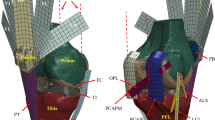

The following ligament structures were included in the model: medial (MCL) and lateral (LCL) collateral ligaments, medial (MPFL) and lateral (LPFL) patellofemoral ligaments, and patellar ligament (PL). The anterior and posterior cruciate ligaments were not included because the first is sacrificed during the surgical procedure, whereas the latter can be excluded since both insert geometries were designed to permit this choice7. Each ligament was furtherly split into different bundles, in detail: MCL anterior (aMCL), intermediate (iMCL) and posterior (pMCL) bundle; LCL anterior (aLCL) and posterior (pLCL) bundle; LPFL proximal (pLPFL), middle (mLPFL) and distal (dLPFL) bundle; MPFL proximal (pMPFL), middle (mMPFL) and distal (dMPFL) bundle; PL medial (mPL), intermediate (iPL) and lateral (lPL). This division allows considering the ligament structure in bundles with their different constraining contribution over the joint movement. Origin and insertion points (Fig. 1) were determined from anatomical references18.

Ligament bundles and muscles included into the multibody model. (a) Lateral view; (b) medial view; (c) frontal view. Red ellipsoids represent tendons of the M. quadriceps femoris and black upward arrows indicate the initial action lines of the Vastus medialis (Vmed), Vastus lateralis (Vlat), Vastus intermedius (Vint), and Rectus femoris (RF).